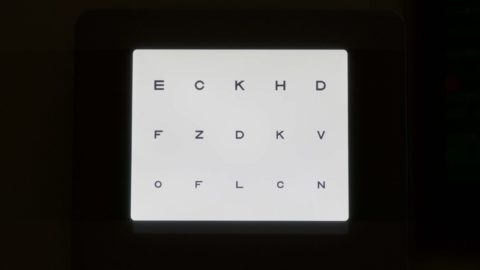

Swissvisio

Brand Content

00:45